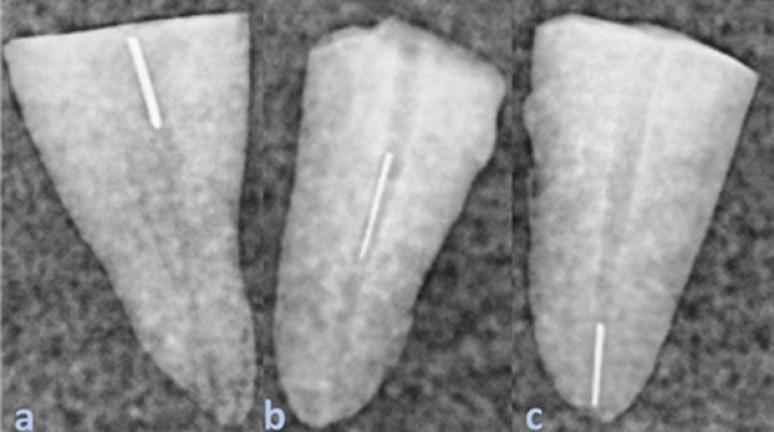

METHODS

180 decoronated single-rooted anterior teeth were divided into four experimental groups (A–D) and one control group (n = 36 each). SS K-files size 15 were fractured in groups A and C, and size 25 in groups B and D at various canal levels. Retrieval in groups A and B used an electromagnetic device; groups C and D used TFRK. In the control group, size 15 Nickel-titanium K-files were used. Retrieval success rates were compared using the Chi-square test, while retrieval times were analyzed using Analysis of Variance (ANOVA) and Tukey’s HSD post hoc test ( ≤ 0.05).